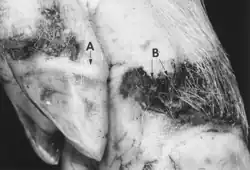

A vesicular lesion begins as a small blanched area and progresses to a blanched, slightly raised area that expands as vesiculation progresses. The epithelium may separate from the stratum basale, leaving a red lesion with shreds of torn epithelium. Vesicular fluid may leak through the stratum corneum without the formation of a true vesicle (Seibold and Sharp 1960). Since vesicles are most often seen at the site of mechanical stress, they usually rupture quickly, leaving a red erosion. Often, lesions are contaminated with dirt and debris (Fig. 25.2), resulting in infection with opportunistic bacteria. The foot lesions, especially of VES, may be associated with a cellulitis with persistent swelling, resulting in lameness and local lymph node involvement. In young animals infected with FMDV, myocardial necrosis may produce pale necrotic areas referred to as "tiger heart."

The clinical signs of FMD, VS, VES, SVD, and SMSV cannot be distinguished from each other in the field. Generally, within 1–5 days postexposure, the body temperature rises sharply to 40.5˚C or higher. Areas of the epithelium become blanched, followed by the formation of vesicles and erosions after loss of the epithelium. Vesicles up to 3 cm in diameter may be found on the snout, with vesicular lesions extending into the nares, on the lips, tongue, hard and soft palate, coronary band, on the soft tissues of the feet (interdigital clefts and bulbs), and soft tissues around the dewclaws (see Figs. 25.1–25.4). Vesicular lesions may occur in other areas of the skin, especially where there is mechanical pressure or abrasion. Nursing sows may have vesicles on the teats. Slobbering and chomping are common. Pregnant sows may abort due to fever. The viruses of FMD, SVD, VES, and VS are not reported to infect the fetus.